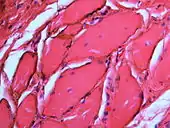

| Amalgam tattoo in upper labial sulcus in an edentulous individual, left behind after teeth have been lost/extracted | |

If necessary, the diagnosis can be confirmed histologically by excisional biopsy, which excludes nevi and melanomas.[3]: 138 If a biopsy is taken, the histopathologic appearance is:[1]

- Pigmented fragments of metal within connective tissue

- Staining of reticulin fibers with silver salts

- A scattered arrangement of large, dark, solid fragments or a fine, black or dark brown granules

- Large particles may be surrounded by chronically inflamed fibrous tissue

- Smaller particles surrounded by more significant inflammation, which may be granulomatous or a mixture of lymphocytes and plasma cells